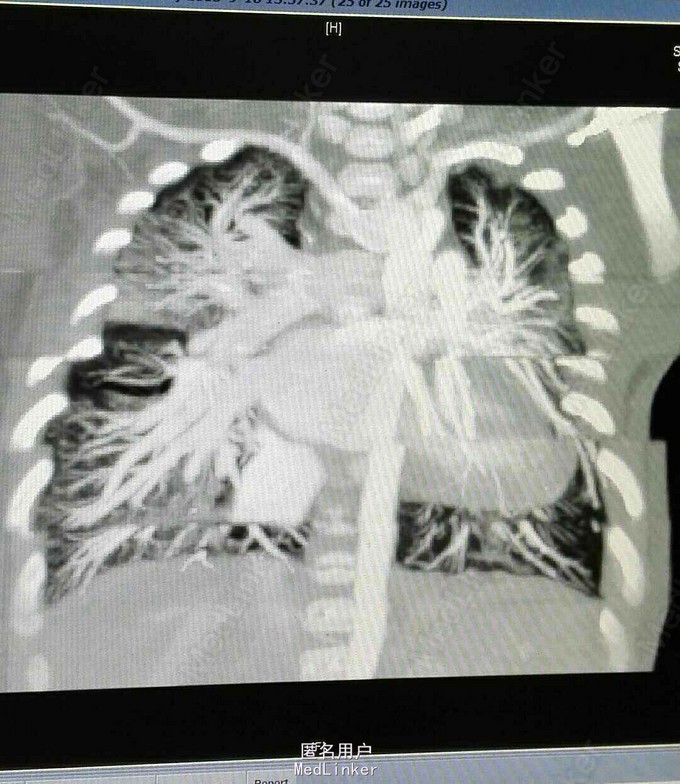

查体 生命体征平稳,双肺呼吸音清,未闻及干湿性罗音,心率规整,于胸骨左缘第二肋间可闻及3/6期收缩期杂音,腹部平软无压痛反跳痛,双下肢无水肿。 辅助检查 心脏彩超示 先天性心脏病 右肺动脉起源于主动脉 动脉导管未闭 三尖瓣反流 肺动脉高压。 心脏CT 先天性心脏病 右肺动脉起源于主动脉 动脉导管未闭 肺动脉高压

诊断 先天性心脏病 右肺动脉起源于主动脉 动脉导管未闭 肺动脉高压 三尖瓣反流 治疗 患者入院后完善各项术前检查及准备在全麻体外循环下行手术治疗 手术过程 仰卧位胸骨正中切口,常规建立体外循环,并体循环下分离并切断缝合动脉导管,充分游离右肺动脉,并将右肺动脉自主动脉离断,6/0丙烯线连续缝合主动脉侧断端。右肺动脉经主动脉下方吻合至主肺动脉侧动脉导管开口。切开右心房,并行下缝合卵圆孔未闭。三尖瓣成型,试水关闭良好,缝合右心房,停机关胸。患者转让监护室治疗2天后转让普通病房术后恢复良好。